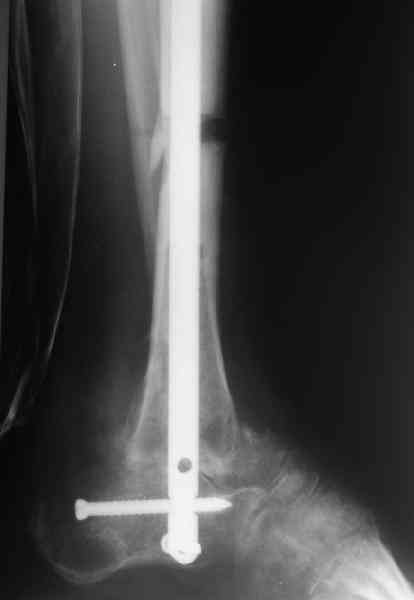

Приветствую, Павел и коллеги, ПИ> удлинения большеберцовой кости для компенсации укорочения поврежденной конечности. ПИ> В итоге: мы планируем выполнить пациенту большеберцово-пяточный ПИ> артродез в аппарате Илизарова с одновременной остеотомией берцовых В продолжение обсуждения, которое было 3 недели назад. Аналогичня операция одному нашему пациенту была сделана в конце февраля 2006. Дистракцию закончили 15 марта. На недавнем снимке нижний регенерат еще довольно хлипкий (снимок 1),

и мы не смогли обещать, что аппарат можно будет совсем скоро снять. Пациент выразил горячее желание расстаться с наружным фиксатором, даже если нужна еще одна операция. На этой неделе выполнили закрытое штифтование (впервые именно в такой ситуации) и сняли аппарат.